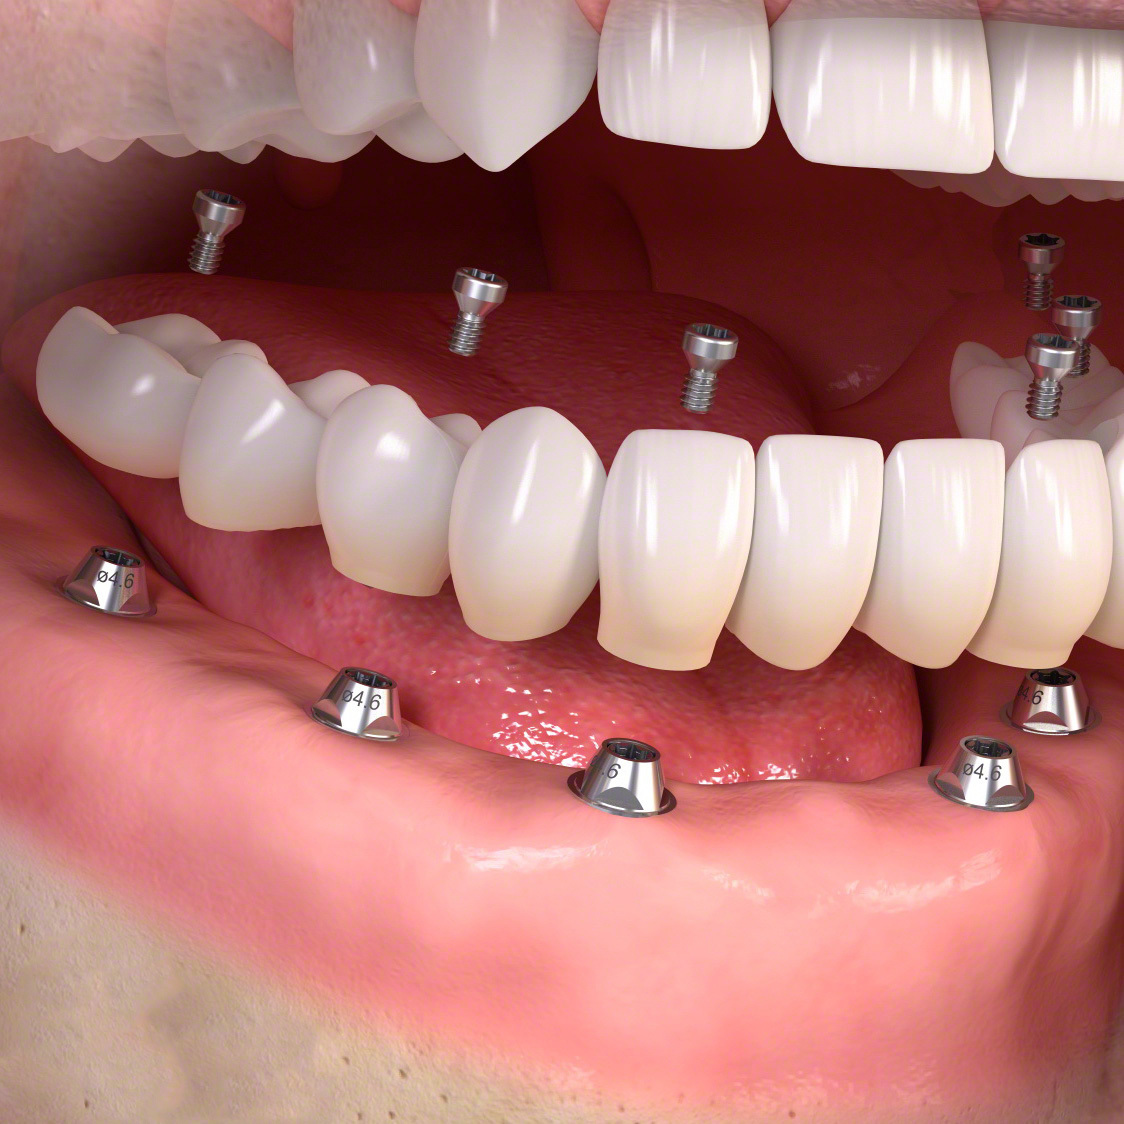

(通常のインプラント法)

歯科インプラントとは、歯を失った部分に人工歯根(主にチタン製)を外科的に埋め込み、その上にセラミックなどで作られた人工の歯を取り付けて、機能と見た目を回復する治療法です。

その後、一次手術としてインプラント体(フィクスチャー)を顎の骨に埋入し、数か月の治癒期間を経て骨としっかり結合させます。治癒後には二次手術を行い、歯肉からインプラントの上部構造を露出させます。なお、骨や歯肉の状態が良好な場合には、一次手術と二次手術を同時に行う「1回法」が選択されることもあります。

傷口が治った後に精密な型取りを行い、上部構造(人工歯)を製作・装着します。

・5~8本のインプラントによって自分の歯のように噛めるよう修復

手術でインプラントを埋める。

人工歯を装着します。

インプラント治療で修復。